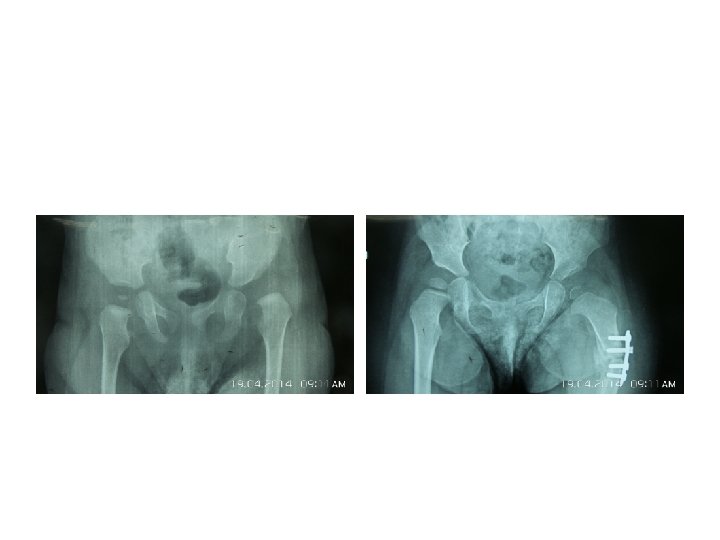

Somerville technique of anterior open reduction in congenital dislocation of hip. A, Bikini incision.

Somerville technique of anterior open reduction in congenital dislocation of hip. A, Bikini incision. B, Division of sartorius and rectus femoris tendons and iliac epiphysis. C, T-shaped incision of capsule. D, Capsulotomy of hip and use of ligamentum teres to find true acetabulum. E, Radial incisions in acetabular labrum and removal of all pulvinar from depth of true acetabulum. F, Reduction and capsulorrhaphy after excision of redundant capsule. G, Developmental dislocation of right hip. H, After anterolateral open reduction. I, At age 7 years; note remodeling of femoral head and acetabulum.